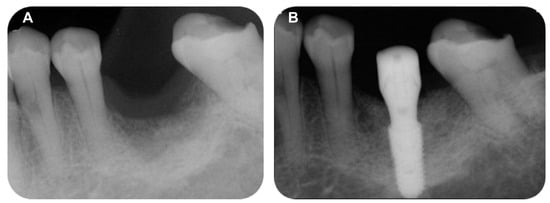

A 69-year-old female patient visited the dental clinic of Daegu Catholic University Medical Center to restore a missing mandibular left first molar and second molar (Figure 8A). The patient had a medical history of mild diabetes and hypertension, but she was not taking any medications which needed to be discontinued during the implant procedure. The patient was a non-smoker. Through consultation with the patient, it was decided that two implants would be placed. As a surgical method, flap operation was planned for vertical and horizontal bone grafting and implant placement. After the intraoral and radiological examination of the patient, scaling was performed before implant placement. The patient received the same pharmacologic protocol of the patient of case 1. A 4.5 × 10.0 mm and a 5.0 × 8.5 mm implant (AR fixture; Biotem, Seongnam, Republic of Korea) were placed, respectively (Figure 8B). Each implant was placed with the proper initial fixation torque of 30 N/cm2. After a sufficient healing period of 3 months, it was decided the prosthetic treatment procedure would commence.

Figure 8. (A) Pre-operative intraoral periapical radiograph, (B) Post-operative intraoral periapical radiograph.